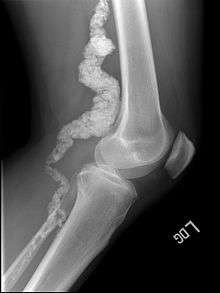

A knee x-ray of a patient with ACDC reveals calcification in the main artery supplying blood to the lower leg.

Arterial calcification due to deficiency of CD73 (ACDC) is a rare genetic disorder that causes calcium buildup in the arteries and joints of the hands and feet, and other areas below the waist.[1] Although patients exhibiting these symptoms have been identified as early as 1914, this disorder had not been studied extensively until recently. The identification of the specific ACDC gene and mutations occurred in 2011. ACDC is caused by a mutation in the NT5E gene, which prevents calcium-removing agents from functioning,.[1][2] Patients afflicted with this mutation suffer from chronic pain, difficulty moving, and increased risk of cardiovascular problems.[1][2] In experiments at the molecular level, treatment with adenosine or a phosphatase inhibitor reversed and prevented calcification, suggesting they could be used as possible treatment methods.[1] There is currently no cure for ACDC, and patients have limited treatment options which focus primarily on removal of blood calcium and improving mobility.[1][2]